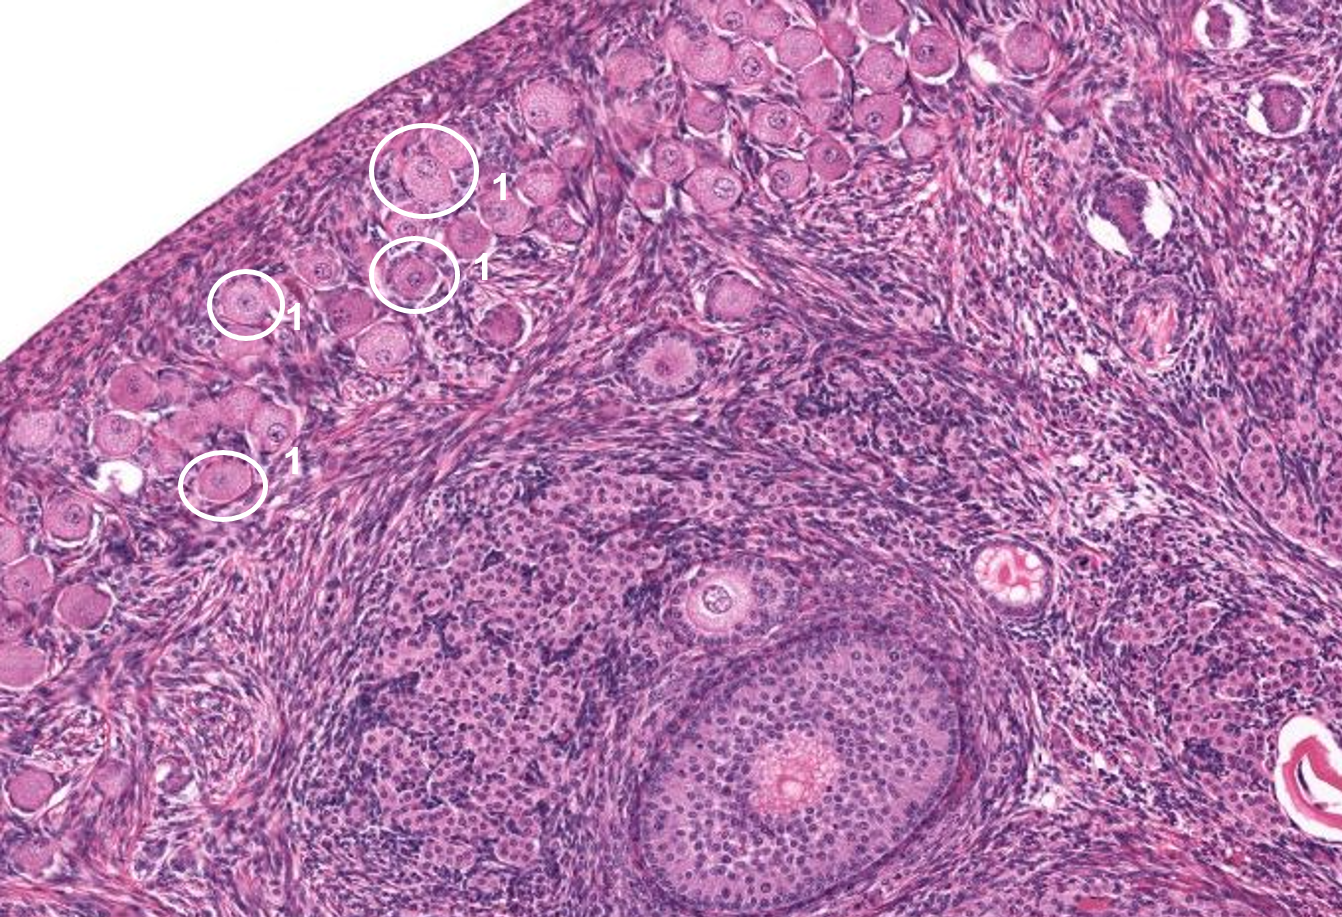

Ovário - folículo primordial

Ovário - folículo de Graff

Ovário - folículo secundário

Ovário